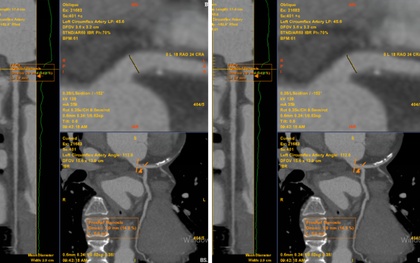

Chỉ đau tức ngực trái thoáng qua, không ngờ phát hiện bệnh lý tim mạch nguy hiểm

Cơn đau kéo dài khoảng 15-20 phút rồi tự hết, nhưng do lo lắng bệnh nhân P.N.K. (58 tuổi, Hà Nội) đi khám và phát hiện bệnh mạch vành.